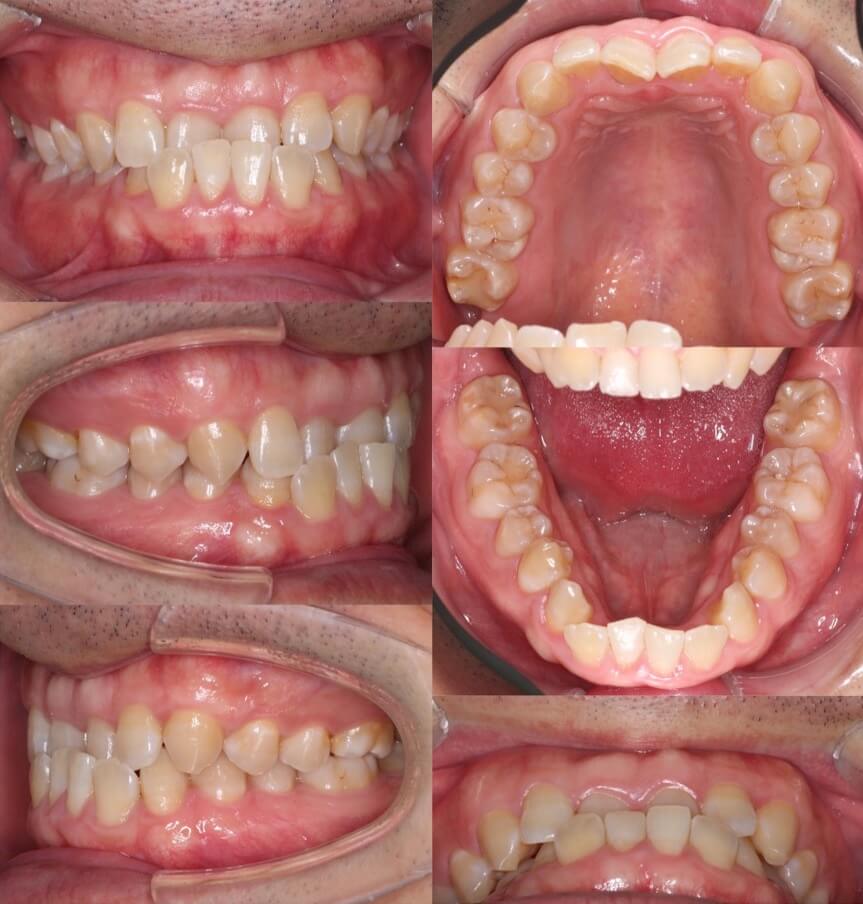

20代女性・唇側矯正装置・上下抜歯

八重歯があり上の歯並びに強いがたつきがある受け口ケースです。反対咬合で小臼歯を抜歯する際は上は5番を抜歯することが多いです。これは、上の前歯を後ろに引きすぎないようにするためです。下の歯並びには前歯の後方移動を効率化するために、2本ワイヤーを使用しています。

<症例概要> 難易度 ★★★★☆

主訴:受け口・前歯のガタガタ

年齢・性別:大学生女性

住まい:千葉県八千代市

症状:反対咬合・重度叢生

治療方針:上下小臼歯抜歯・上顎歯列拡大・空隙閉鎖

治療装置:唇側矯正装置

固定装置:上リンガルアーチ・III級顎間ゴム

抜歯:上第二小臼歯・下第一小臼歯(計4本)

治療期間:2年3か月

リテーナー:上下フィックスタイプ+プレートタイプ

治療費用:990,000(税込)

代表的副作用:痛み・治療後の後戻り・歯根吸収・歯髄壊死・歯肉退縮